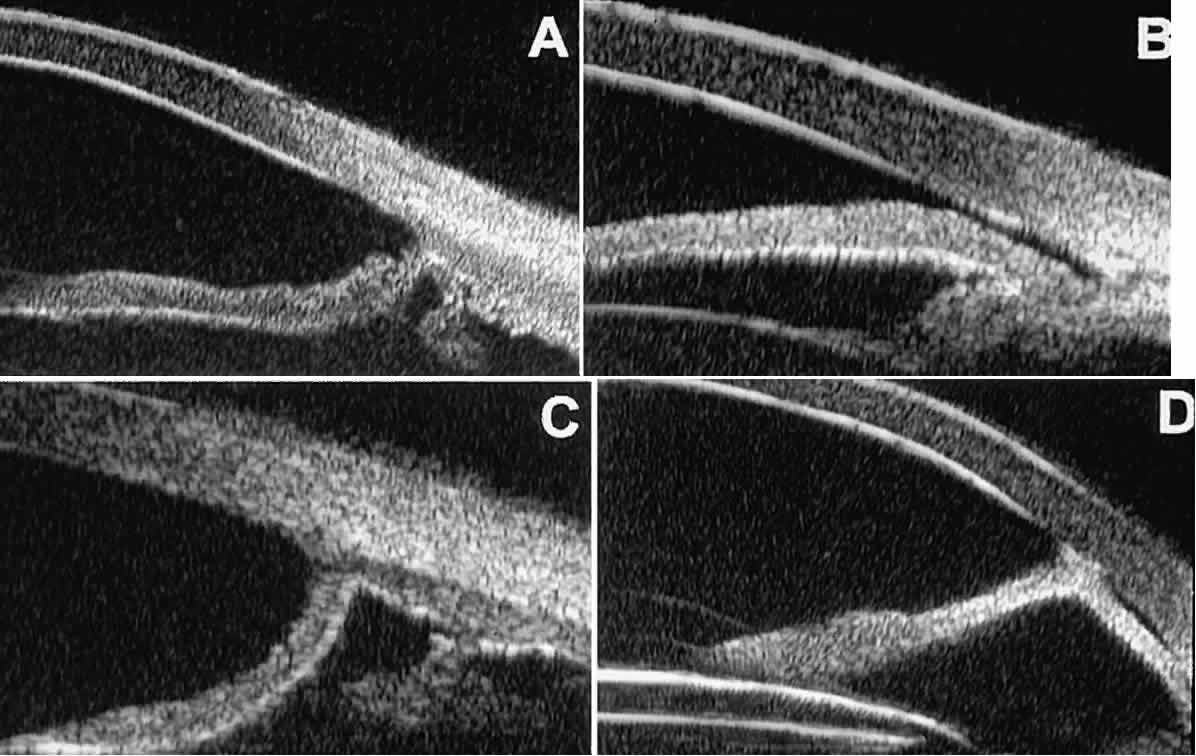

Postoperative UBM imaging of the anatomic changes caused by glaucoma surgery

often helps to explain mechanisms of success and failure of the

various surgical procedures (Fig. 12).3,4 After laser iridotomy, UBM can show whether the iridotomy is partial thickness (see Fig. 12A) or full thickness (see Fig. 12B) and whether the plane of curvature of the peripheral iris has changed

compared with the pretreatment findings. After trabeculectomy (see Fig. 12C), UBM can show whether the scleral aperture is patent or blocked internally, whether

the peripheral iridectomy is open or blocked, and whether

the filtering bleb is flat, shallow, or deep.9 After tube shunt surgery (see Fig. 12D), UBM can show the position of the tip of the tube and whether its orifice

is open or plugged.  Fig. 12. UBM features in glaucomatous eyes after treatment or filtering surgery. A. Incomplete peripheral iridectomy created by laser. B. Full-thickness peripheral iridectomy created by laser. C. Postoperative features of trabeculectomy including peripheral iridectomy, inner

scleral defect, thin residual scleral flap, and overlying conjunctival

filtering bleb. D. Tube shunt projecting radially into anterior chamber; note that the tube “shadows” deeper structures. Fig. 12. UBM features in glaucomatous eyes after treatment or filtering surgery. A. Incomplete peripheral iridectomy created by laser. B. Full-thickness peripheral iridectomy created by laser. C. Postoperative features of trabeculectomy including peripheral iridectomy, inner

scleral defect, thin residual scleral flap, and overlying conjunctival

filtering bleb. D. Tube shunt projecting radially into anterior chamber; note that the tube “shadows” deeper structures.